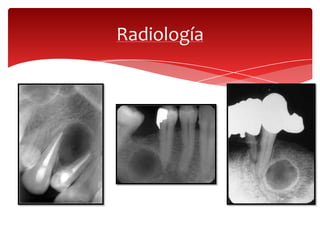

Radiología

Se presenta una radiolucidez

redondeada, bien circunscrita, en

el vértice de la raíz de un diente

desvitalizado.